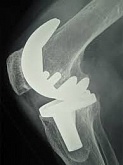

Еndoprosthesis of knee joint

In the late stages of arthrosis of the knee joint, accompanied by a pronounced restriction of the volume of movements, constant intense pain, deformity of the limb, the only way to recover is to replace the affected joint with an artificial joint - arthroplasty.

This method allows you to return the correct form of the limb, the full volume of movements in the joint, relieve the constant pain and crunch during movements and, as a result, significantly improve the patient's quality of life.

Below are presented X-ray photographs and photographs, illustrating the amount of motion in the affected joint before and after surgery.